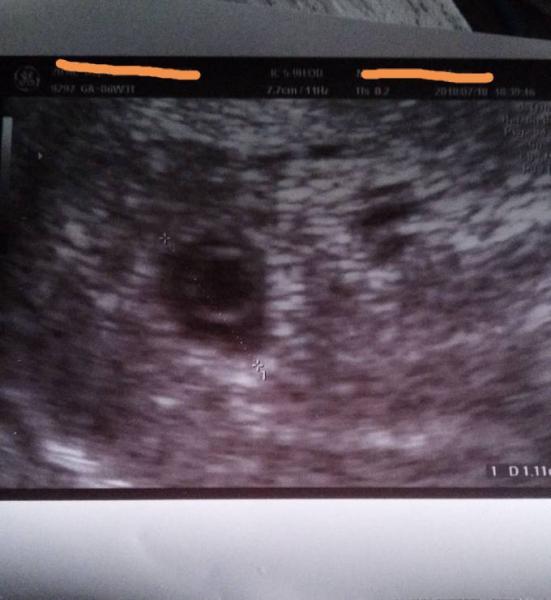

Ich hatte jetzt kurzzeitig den Gedanken, belt heute noch zu nem anderen Arzt zu gehen. Bisher ist die Blutung schwach, aber ich hab schon Kreuzschmerzen, wie bei jeder anderen FG auch. Hab Magnesium genommen und nehme globuli, aber da die Entwicklung nicht zeitgerecht ist, wird das wohl auch nix nutzen. Weiß grad echt nicht weiter. Hänge mal das Bild von gestern hier an. Die Form der Fruchthöhle ist auch arg seltsam. Sah vorher nie so aus. Und wie riesig der Dottersack in der kleinen Fruchthöhle ist, ist doch auch nicht normal. Trotzdem danke für die lieben Antworten.

Bild zu Ich nochmal - Forum für März - Mamis